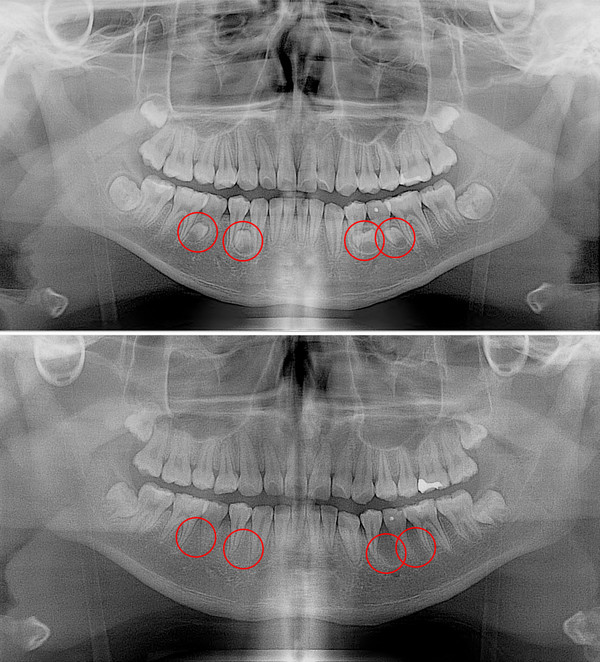

그러던 중 몇 년 전 치과 X-ray 촬영에서 과잉치가 발견되었고, 시간이 지나면서 치아 배열이 점점 더 불규칙해져서 씹을 때도 어려움을 겪고 있다.

과잉치가 발생하는 정확한 원인은 밝혀지지 않았다. 다만 부모나 형제에게 과잉치가 있으면 발생 확률이 높아지는 것으로 보고 있다. 대부분이 턱뼈 내에 매복돼 있기 때문에 당사자 또는 보호자가 미리 알기는 매우 어렵다. 파노라마 방사선 촬영과 근단 방사선 사진 촬영, CT 촬영 등을 통해서만 발견할 수 있다.